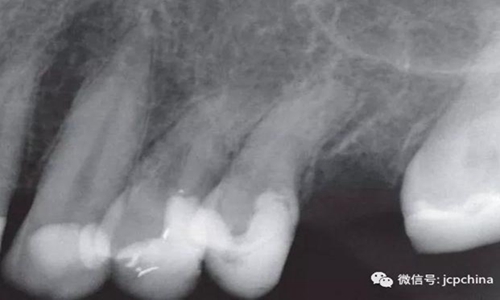

如圖所示,由于很難將圖像傳感器放置在理想的位置,造成圖像失真。當(dāng)對左上前磨牙進(jìn)行拍攝時(shí),由于淺腭穹隆的解剖結(jié)構(gòu)限制,無法進(jìn)行平行投照。